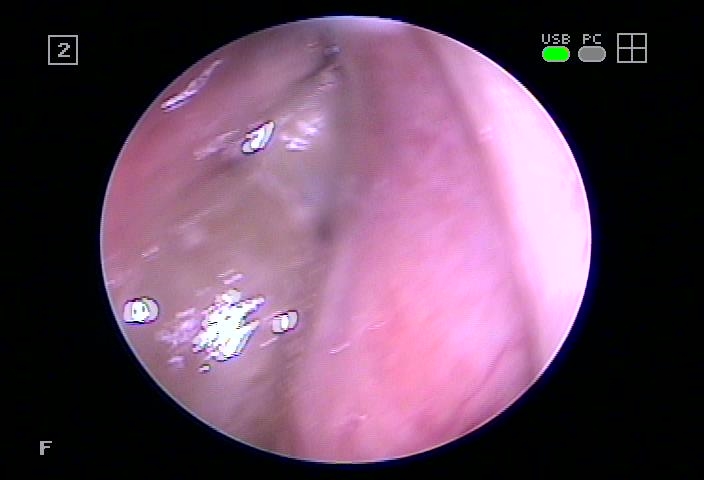

입냄새까지 유발할 수 있어요.해당 질환의 경우 콧물과 코막힘, 재채기 등을 동반하게 되며 누적된 고름으로 인해 입냄새까지 일으킬 수 있으므로 주의해야 한다고 했습니다. 이 병변의 경우 얼굴 뼈 사이에 존재하는 빈 공간의 점막에 염증이 나타나게 되는 것으로 이곳은 코와 자연공으로 연결돼 있는데 이때 선행되는 질환으로 인해 이행하는 경우가 많았습니다.

대부분의 사람이 감기나 급성비염을 오랫동안 겪게 되면서 자연공이 폐쇄되고 원활한 순환이 이루어지지 않아 발병하게 되는 것으로 수원축농증이비인후과에서는 부비동 내 점막에는 염증이 발현하게 되어 노란 콧물과 함께 안면부 통증이나 다른 곳까지 좋지 않은 영향을 미친다고 하였습니다.

특히 반복적으로 형성되면 해당 환부가 호흡기 질환이 이행되어 보이는 것이기 때문에 비강 내 점막을 직접 자극하여 부종을 진정시키고 자연공을 관리하는 것을 보게 되었습니다.

따라서 수원축농증이비인후과에서는 부종으로 인해 부어있는 점막을 관리하고 이를 완화하는 자극요법으로 비강 내에 쌓여있는 노폐물을 제거하여 자연스러운 자연공의 개방을 이끌어낼 수 있었습니다.